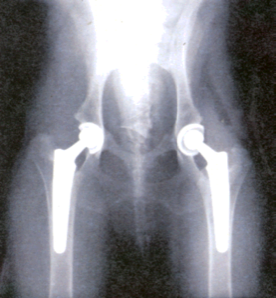

Los tratamientos conservadores que un traumatologo ortopedista realiza pueden ser las reducciones incruentas, vendajes blandos, la colocación de férulas y yesos asi como tracciones blandas ó esqueléticas. Los tratamientos quirúrgicos implican una acción sobre situaciones de mayor gravedad o que requieran cirugía como único medio de solución. Para ello se emplean: la reducción abierta, agujas de Kirschner y Steinmann, placas y tornillos de osteosíntesis, dispositivos clavo-placa y tornillo-placa, clavos intramedulares (Küntscher, Gross-Kempf, Ender, Russ), fijadores externos (Hoffman, Ilizarov, monolaterales), injertos óseos, cementos óseos y prótesis para reemplazos articulares.